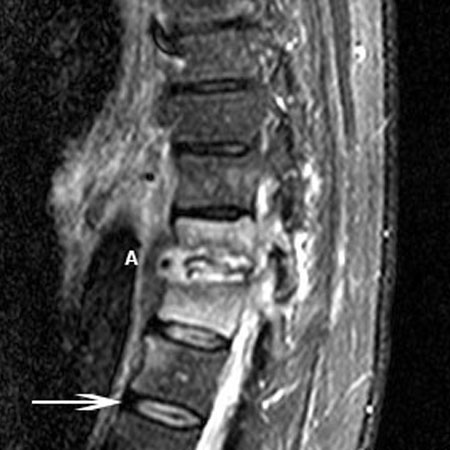

Magnetic resonance imaging of osteomyelitis: T11-T12 disk space is involved with discitis (A). There is bony involvement of both vertebrae indicated by high T2 signal of the vertebral bodies. Arrow indicates a normal healthy vertebral disk

Courtesy of Dr K. Singh; used with permission